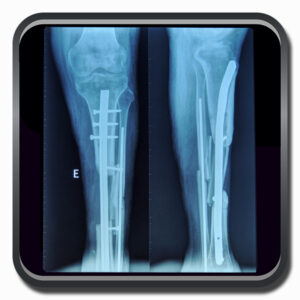

Algumas Cirurgias Complexas realizadas por profissionais da COFIB: